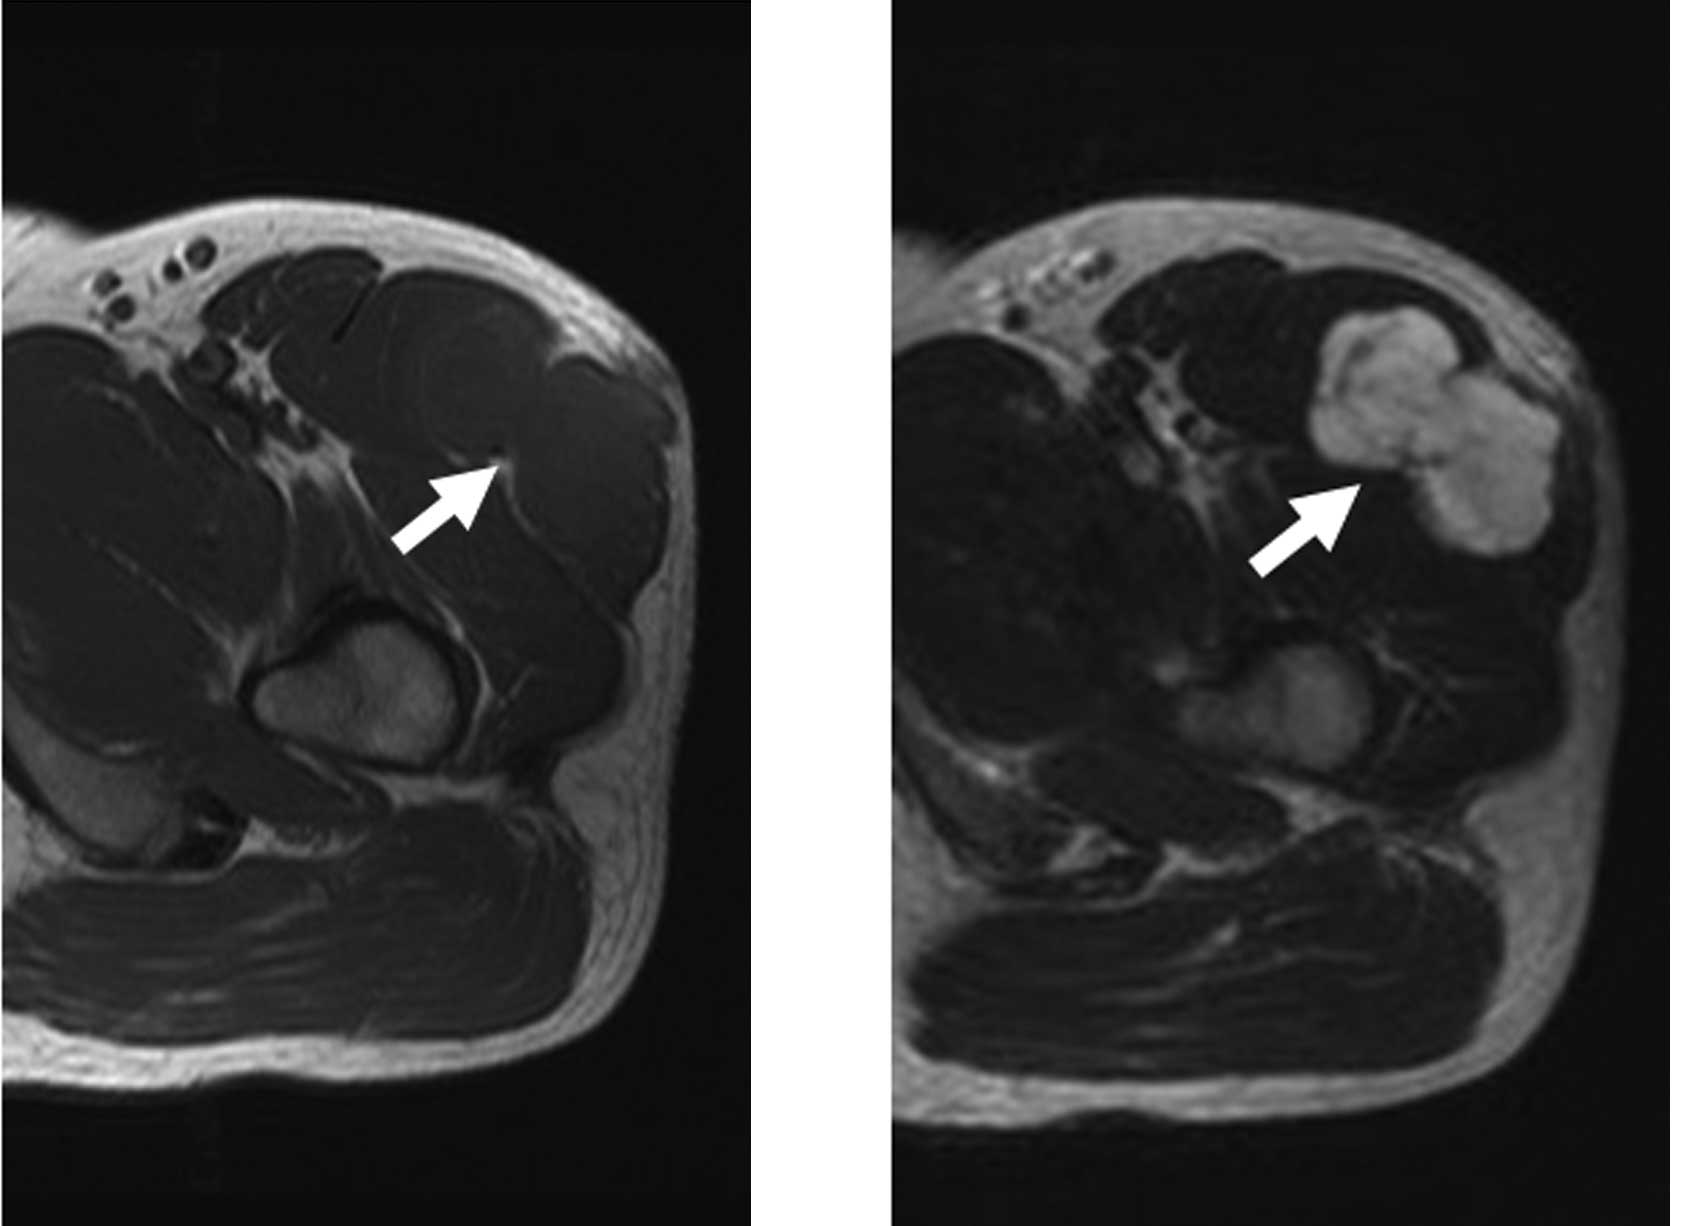

Extraskeletal myxoid chondrosarcoma of the thigh with a t(9;17) translocation

Extraskeletal myxoid chondrosarcomas (EMC) are relatively rare. We report a case of EMC of the thigh. A 41-year-old man presented with a tumor history of more than 4 months. Following open biopsy, wide resection of the tumor was performed. Histopathologically, the tumor had a multinodular architecture consisting of myxomatous areas demarcated by fibrous septa. Proliferation of uniform, round tumor cells with oval nuclei was observed. Well-formed hyaline cartilage and rhabdoid-like cells were not visible. Immunohistochemically, the tumor cells were positive for vimentin and S-100. The composite karyotype was 46,XY,t(9;17)(q22;q11),t(9;21)(q21;p13), and the diagnosis of EMC was made. No recurrence of the mass or metastasis was observed during a follow-up period of 4 years and 7 months. Only 50 cytogenetic cases of EMC, including our case, have been reported in the English literature thus far. Clinical presentation, radiological features and histopathological and cytogenetic findings are described, and the relevant literature is reviewed.

Figure 2